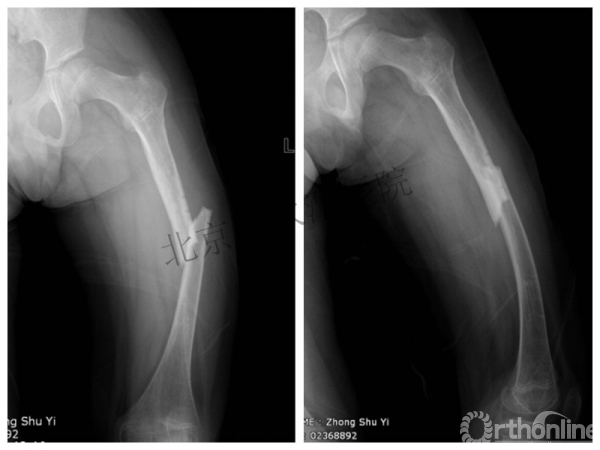

男孩 、5岁,初次骨折于2007年7月。

术后2年→再骨折→再次手术

钢板固定后一年

取板后再骨折→TEN

TEN取出后2个月

闭合复位再固定加尾帽

又过了4年!时间来到2015年

一年以后顺利愈合,实则危机四伏

数月后再骨折!牵引!

髋人字支具

外固定架术后一年

整整11年!是否治疗终结?

病人的付出?医生当反思!